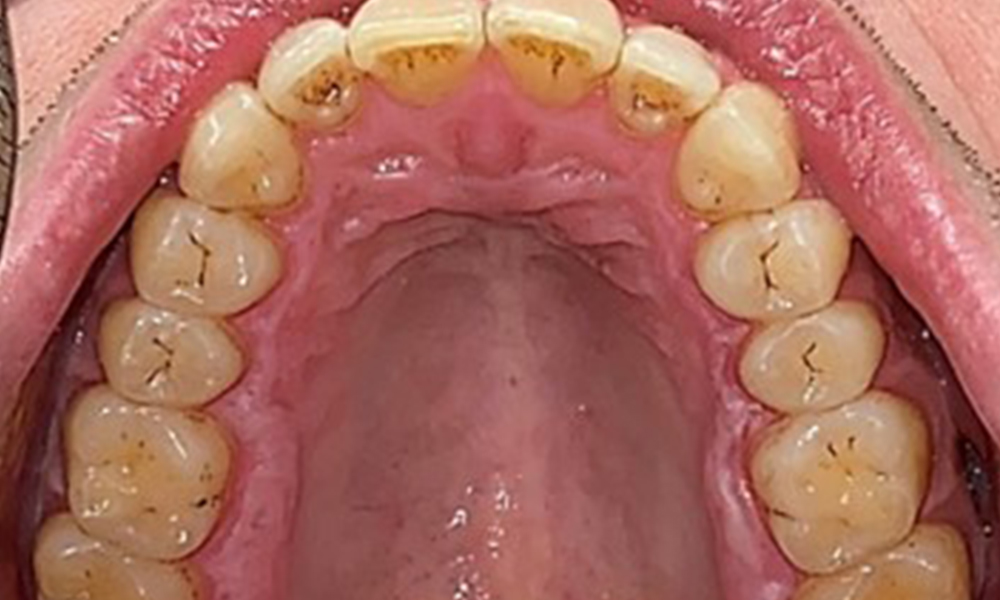

Dental zeigt sich ein vollbezahntes Gebiss mit 28 Zähnen. Auffällig sind Erosionen und Attritionen

(Abb. 4, Abb. 5). Der Patient trägt seit vielen Jahren nachts eine Schiene mit adjustiertem Aufbiss aufgrund Bruxismus. Die Erosionen sind auf den langjährigen Konsum isotonischer Getränke zurückzuführen. Parodontaler Knochenverlust und aktive kariöse Läsionen sind nicht vorhanden.